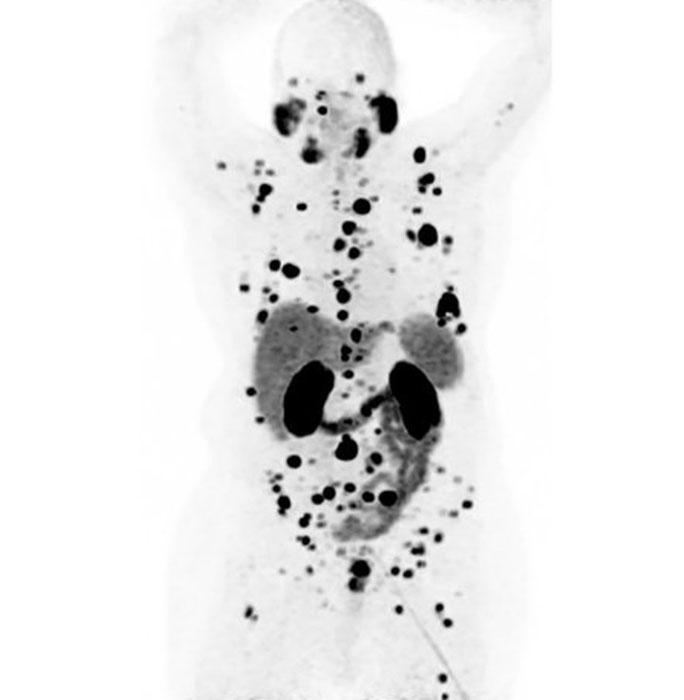

That PSMA is what the radioactive molecules lutetium-177 PSMA and gallium-68 PSMA attach to. In the case of gallium-68 PSMA, this radiotracer contains a low amount of radiation that lights up the cancer cells on a positron emission tomography (PET) scan so that we can see where the cancer has spread and whether it binds to the radiotracer.

If the cancer cells do light up, that tell us they will also bind to lutetium-177 PSMA, which contains a similar PSMA tracer but a stronger type of radiation.

The PSMA PET imaging test is a specific type of scan that shows us where in the body the cancer is by using the gallium-68 PSMA radiotracer.

After an hour, which gives time for the radiotracer to travel throughout the body, you’ll lie still on the PET table for roughly 25 minutes as the machine scans your body. Those images are then sent to your nuclear medicine physician for evaluation, who sends a report on the images to your cancer doctor.